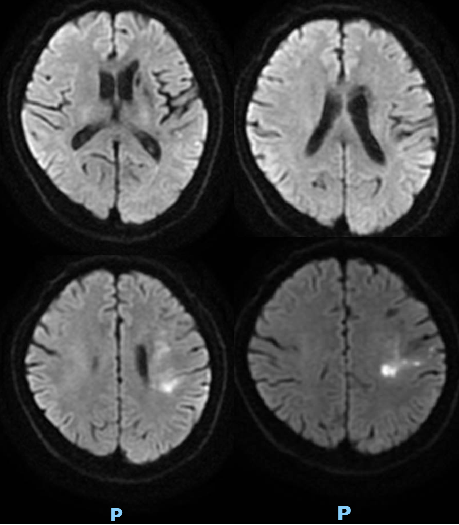

入院影像检查

导丝怎么扩【载药时代 球扩天下】NOVA DES®颅内药物洗脱支架在颅内富穿支区域使用体会二例!_https://www.jmylbn.com_新闻资讯_第28张

DWI

重要影像结论:脑干梗死灶。

导丝怎么扩【载药时代 球扩天下】NOVA DES®颅内药物洗脱支架在颅内富穿支区域使用体会二例!_https://www.jmylbn.com_新闻资讯_第29张

导丝怎么扩【载药时代 球扩天下】NOVA DES®颅内药物洗脱支架在颅内富穿支区域使用体会二例!_https://www.jmylbn.com_新闻资讯_第30张

DSA

重要影像结论:基底动脉重度狭窄。